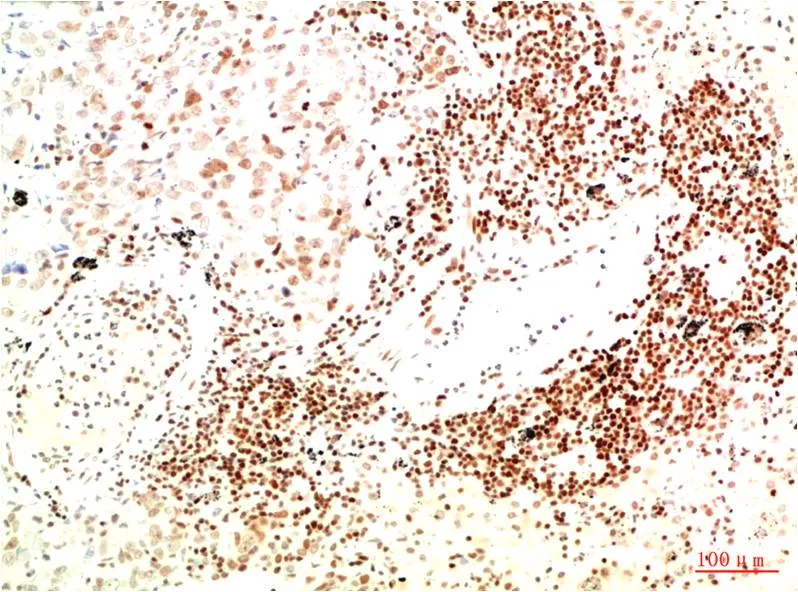

HDAC1 (3F5) Mouse Monoclonal Antibody

Cat: AMM03343

Application:IHC-P

Reactivity:Human,Rat,Mouse

Conjugate:Unconjugated

Gene Name:HDAC1